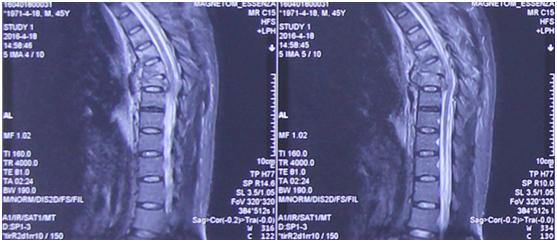

影像学资料

“当患者入院后,我们发现整个脊柱已经完全断掉,而且不是一个横断,是一个斜型的断裂,斜向骨折线上下两个椎体已经完全错开。”李维新教授表示:“这种高能量损伤对脊柱损伤非常大,同时伴有大量的血气胸,病人呼吸困难生命垂危,因为胸腔里全是血,脊髓也受到严重的挫伤,造成患者脊柱损伤的话这个力量是非常大的。”